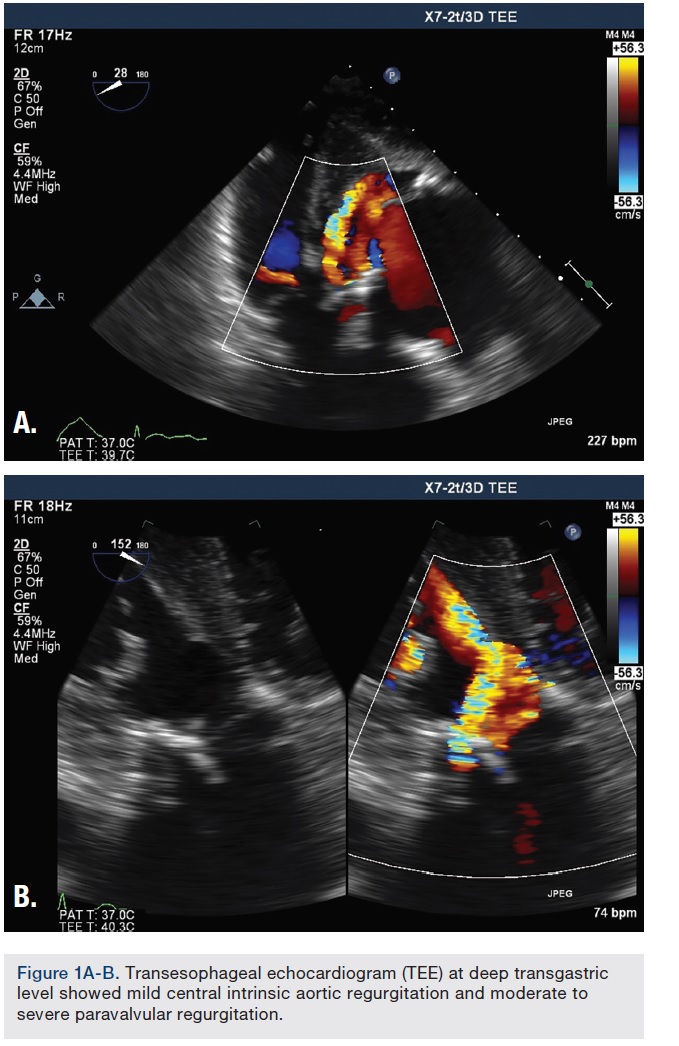

The procedure was performed under deep sedation with use of intravenous (IV) propofol. Transesophageal echocardiography (TEE) was utilized to assist in the closure of the aortic paravalvular leak (PVL). TEE confirmed a bioprosthetic aortic valve with mild central intrinsic regurgitation, and moderate to severe paravalvular regurgitation (Figure 1A-B). The paravalvular regurgitation was found at the lateral aspect of the aortic annulus (Figure 2).